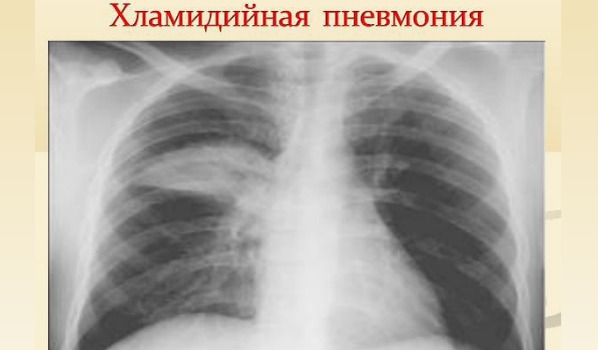

Що стосується рентгенограми, то для всіх видів атипової пневмонії характерні неяскраві прояви на рентгенівському знімку. При мікоплазмовій пневмонії можна побачити розмиті світлі області, при хламідійної рентгенівські знімки показують вид запалення легенів.